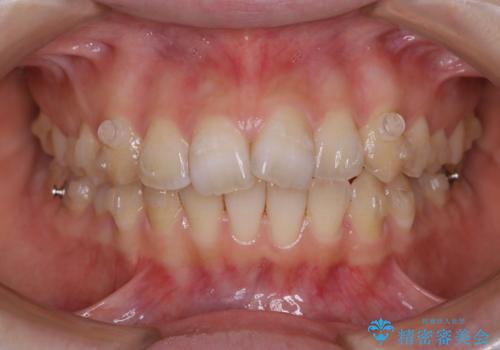

前歯の重なりは奥歯のズレが原因:まとめてインビザラインで治す

- 前歯の重なりが気になるとご相談にいらした方です。前歯のがたつきは奥歯の噛み合わせのズレが原因となっていたため、インビザラインFULLにて奥歯からしっかり治療していきました。